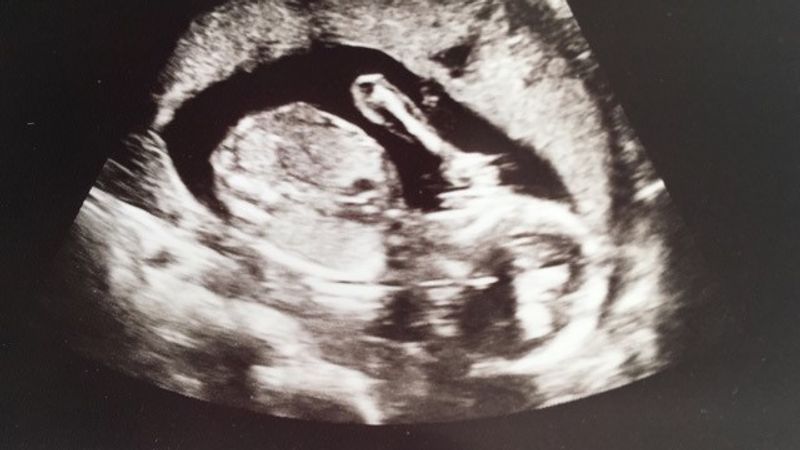

Dan ben je er, word je op bed gelegd en weet je: binnen nu en drie minuten word ik geholpen. Dat werden dus 30 minuten (minstens). Nu had mijn moeder gelijk met ‘een bevalling heeft voorrang’, maar ik was misschien wel mijn baby verloren. Verloren. Ik trok het gewoon niet meer. Ik werd ook steeds onaardiger tegen de verpleegkundige (sorry mevrouw). “Nee ik wil niets eten”. “Nee ook niks drinken” (Grrrr). Eindelijk kwam daar de gynaecologe aan, met een stagiaire. Ze heeft een echo apparaat bij zich en zet het vrijwel meteen op mijn buik. Er klopt een hartje. Er klopt een hartje. Tranen. “Sorry dat ik huil”. Mijn moeder belt meteen Erik. “Mam, dit is wel erg onbeleefd” (maar wel het goede). Er zat nog steeds een klein meisje in mijn buik. Ik ga het ziekenhuis niet uit zonder baby. Ik ga het ziekenhuis uit met baby Sophie in mijn buik. Wat volgde waren veel onderzoeken, ook inwendige echo’s (bleh), maar geen resultaten. Ze kon niks vinden en na een paar uur mocht ik weer naar huis. Precies tijdens de spits, maar ach. Sophie zit in mijn buik. Ik moest alleen een beetje rustig aan doen de komende dagen.